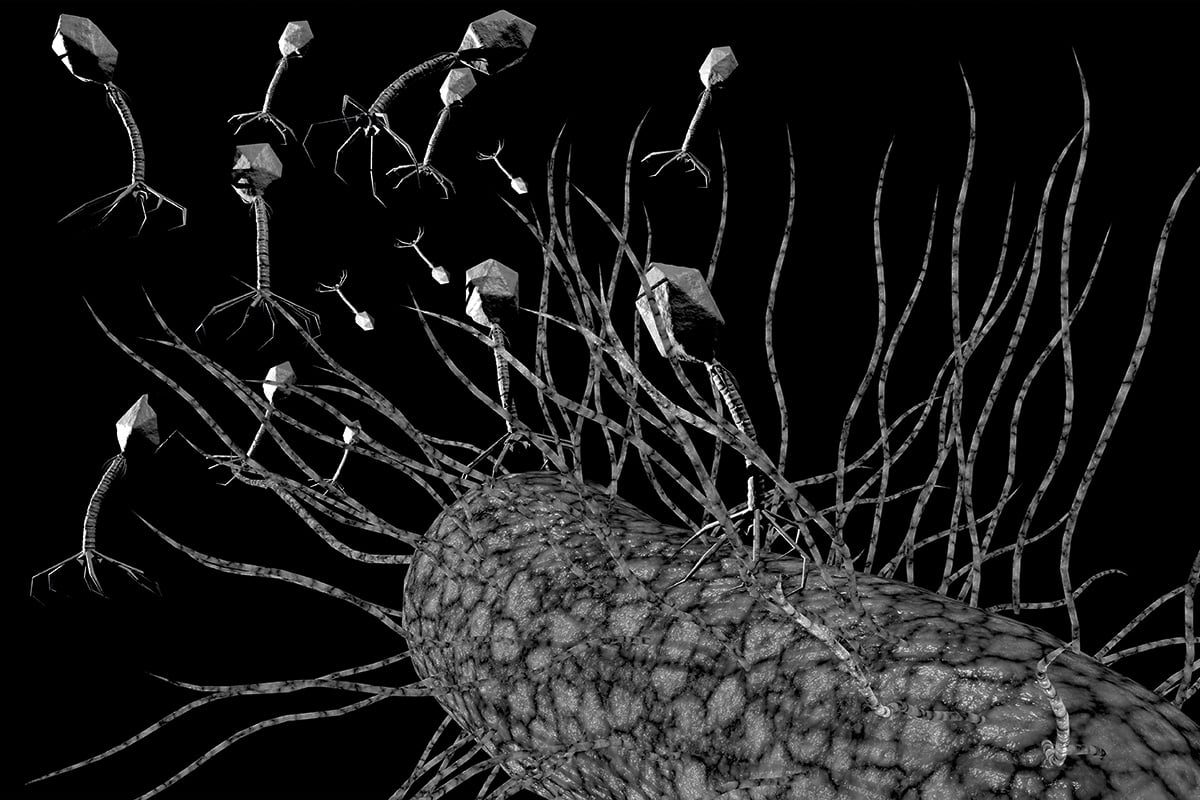

Les bactériophages sont des virus, qui ne s’attaquent qu’aux bactéries et qui sont inoffensifs pour les cellules humaines. Ils ont déjà éliminé avec succès des infections bactériennes chez l’humain, mais ce type de traitement est encore peu utilisé dans les hôpitaux. Illustration: Shutterstock

Ces virus, qui ne s’attaquent qu’aux bactéries et sont inoffensifs pour les cellules humaines, ont déjà éliminé avec succès des infections bactériennes – brûlures, ulcères et plaies infectées – chez certains malades, notamment en Géorgie, un petit pays du Caucase. Mais cette thérapie n’a encore jamais été utilisée aux États-Unis. Pourrait-elle sauver son mari ?

Les bactériophages attaquent leur cible selon différentes stratégies. Certains emploient une attaque directe : ils se fixent à la bactérie, y pénètrent, s’y multiplient, puis la font exploser en libérant de nouveaux bactériophages. C’est ce qu’on appelle le mode lytique.

D’autres adoptent une stratégie plus sournoise, insérant leur matériel génétique dans celui de la bactérie en attendant le bon moment avant de la détruire. C’est le mode prophage. Il n’est pas rare que les bactériophages passent du mode lytique au mode prophage, et inversement, en fonction des conditions.

En parallèle, le chercheur travaille aussi à étendre le spectre d’action des phages. Normalement, un bactériophage cible une espèce bactérienne précise, en s’y fixant grâce à des protéines de reconnaissance sur sa « queue ». En modifiant ces protéines, Louis-Charles Fortier espère forcer un type précis de bactériophage à s’accrocher à un large éventail de bactéries résistantes aux antibiotiques.